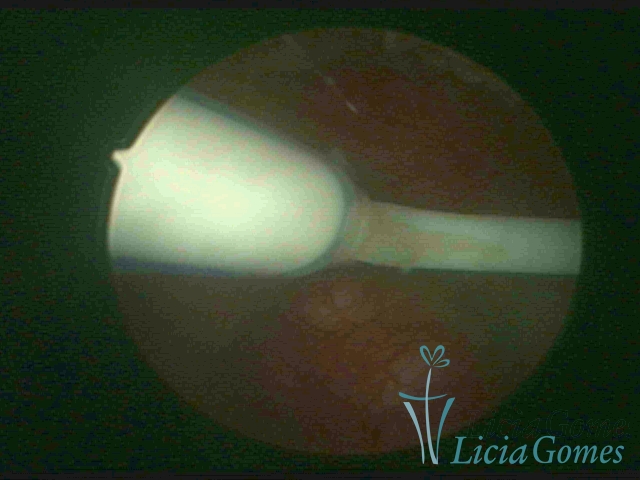

Canal cervical com fio do DIU